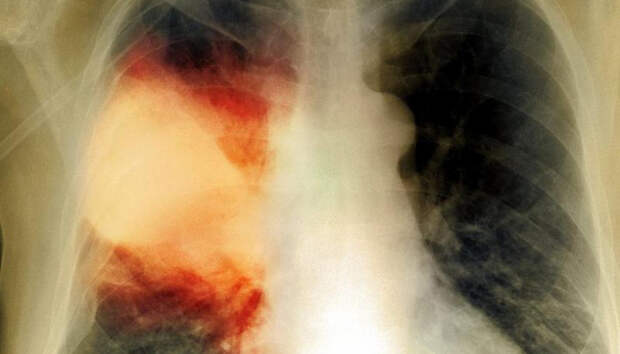

Летальных исходов от воспаления легких не зарегистрировано Пять человек за сутки госпитализированы с внебольничной пневмонией в Карелии, сообщает оперштаб по борьбе с распространением коронавирусной инфекции. Летальных исходов не зарегистрировано. Начиная с 1 апреля, с внебольничной пневмонией госпитализированы 1397 пациентов, 78 человек умерли (с учетом пациентов, госпитализированных ранее указанного периода).